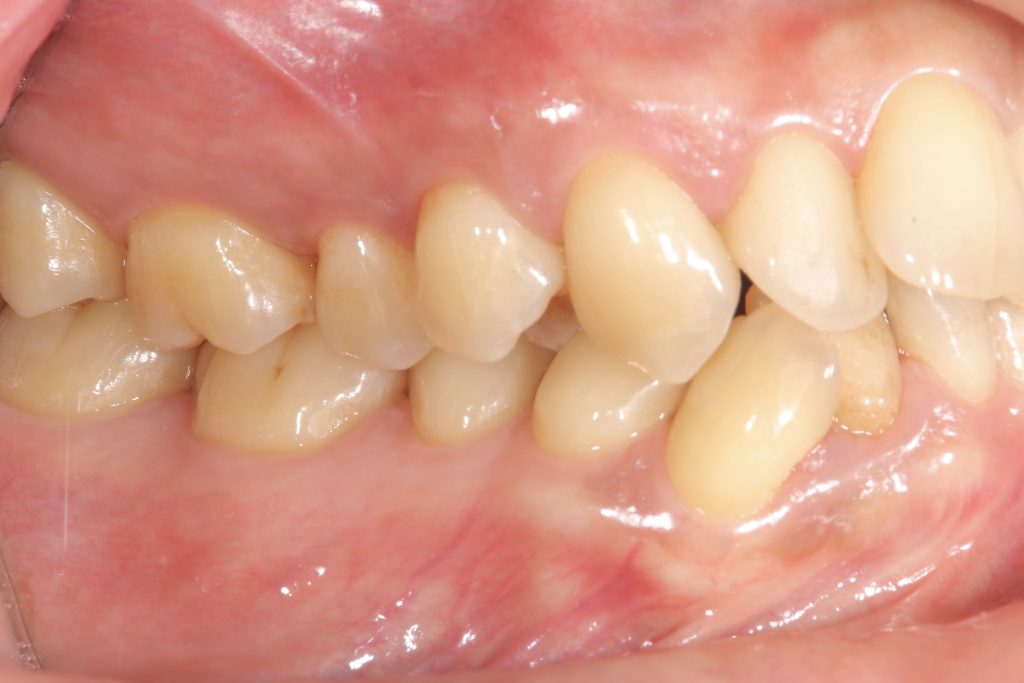

受け口の状態により、上の歯が内側に入り込み、反対の噛み合わせになっている部分が見られました。見た目の問題だけでなく、噛み合わせのバランスにも影響を与えていました。

- 前歯部交叉咬合を伴う不正咬合

- ゴムメタルワイヤー矯正

- 2024年9月6日(10ヶ月)